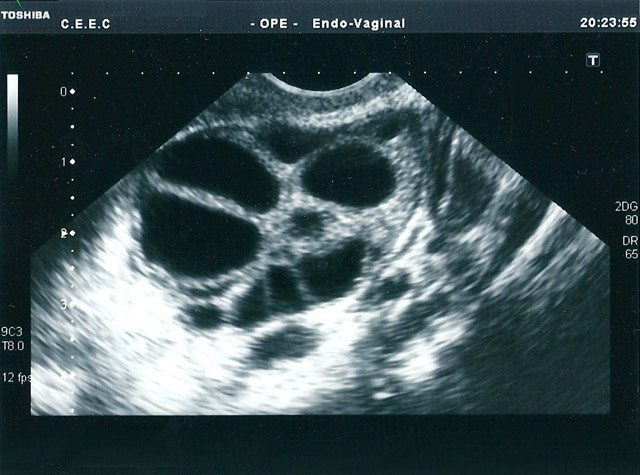

inicialexames a clinicapreçáriogaleriaFAQcontactos